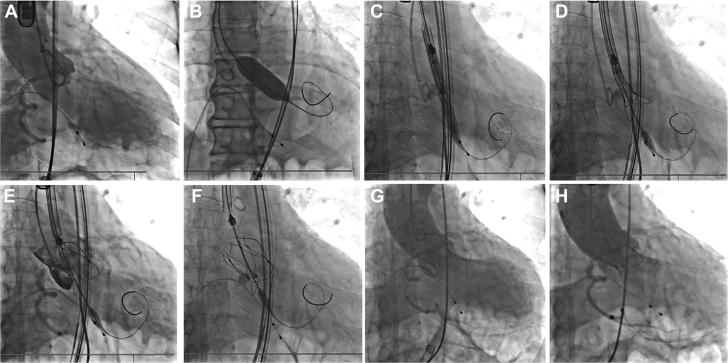

The indication for transcatheter aortic valve replacement to younger patients remains controversial. Here, we report a successful implantation of the first polymeric transcatheter aortic valve replacement device in a patient with severe calcific aortic stenosis. Compared with conventional valves, the novel valve has better durability, larger orifice area, and better morphological adaptability. ().

对于年轻患者进行经导管主动脉瓣置换术的适应症仍存在争议。在此,我们报告了首例聚合物经导管主动脉瓣置换装置在一名重度钙化性主动脉瓣狭窄患者中的成功植入。与传统瓣膜相比,这种新型瓣膜具有更好的耐用性、更大的开口面积和更好的形态适应性。()